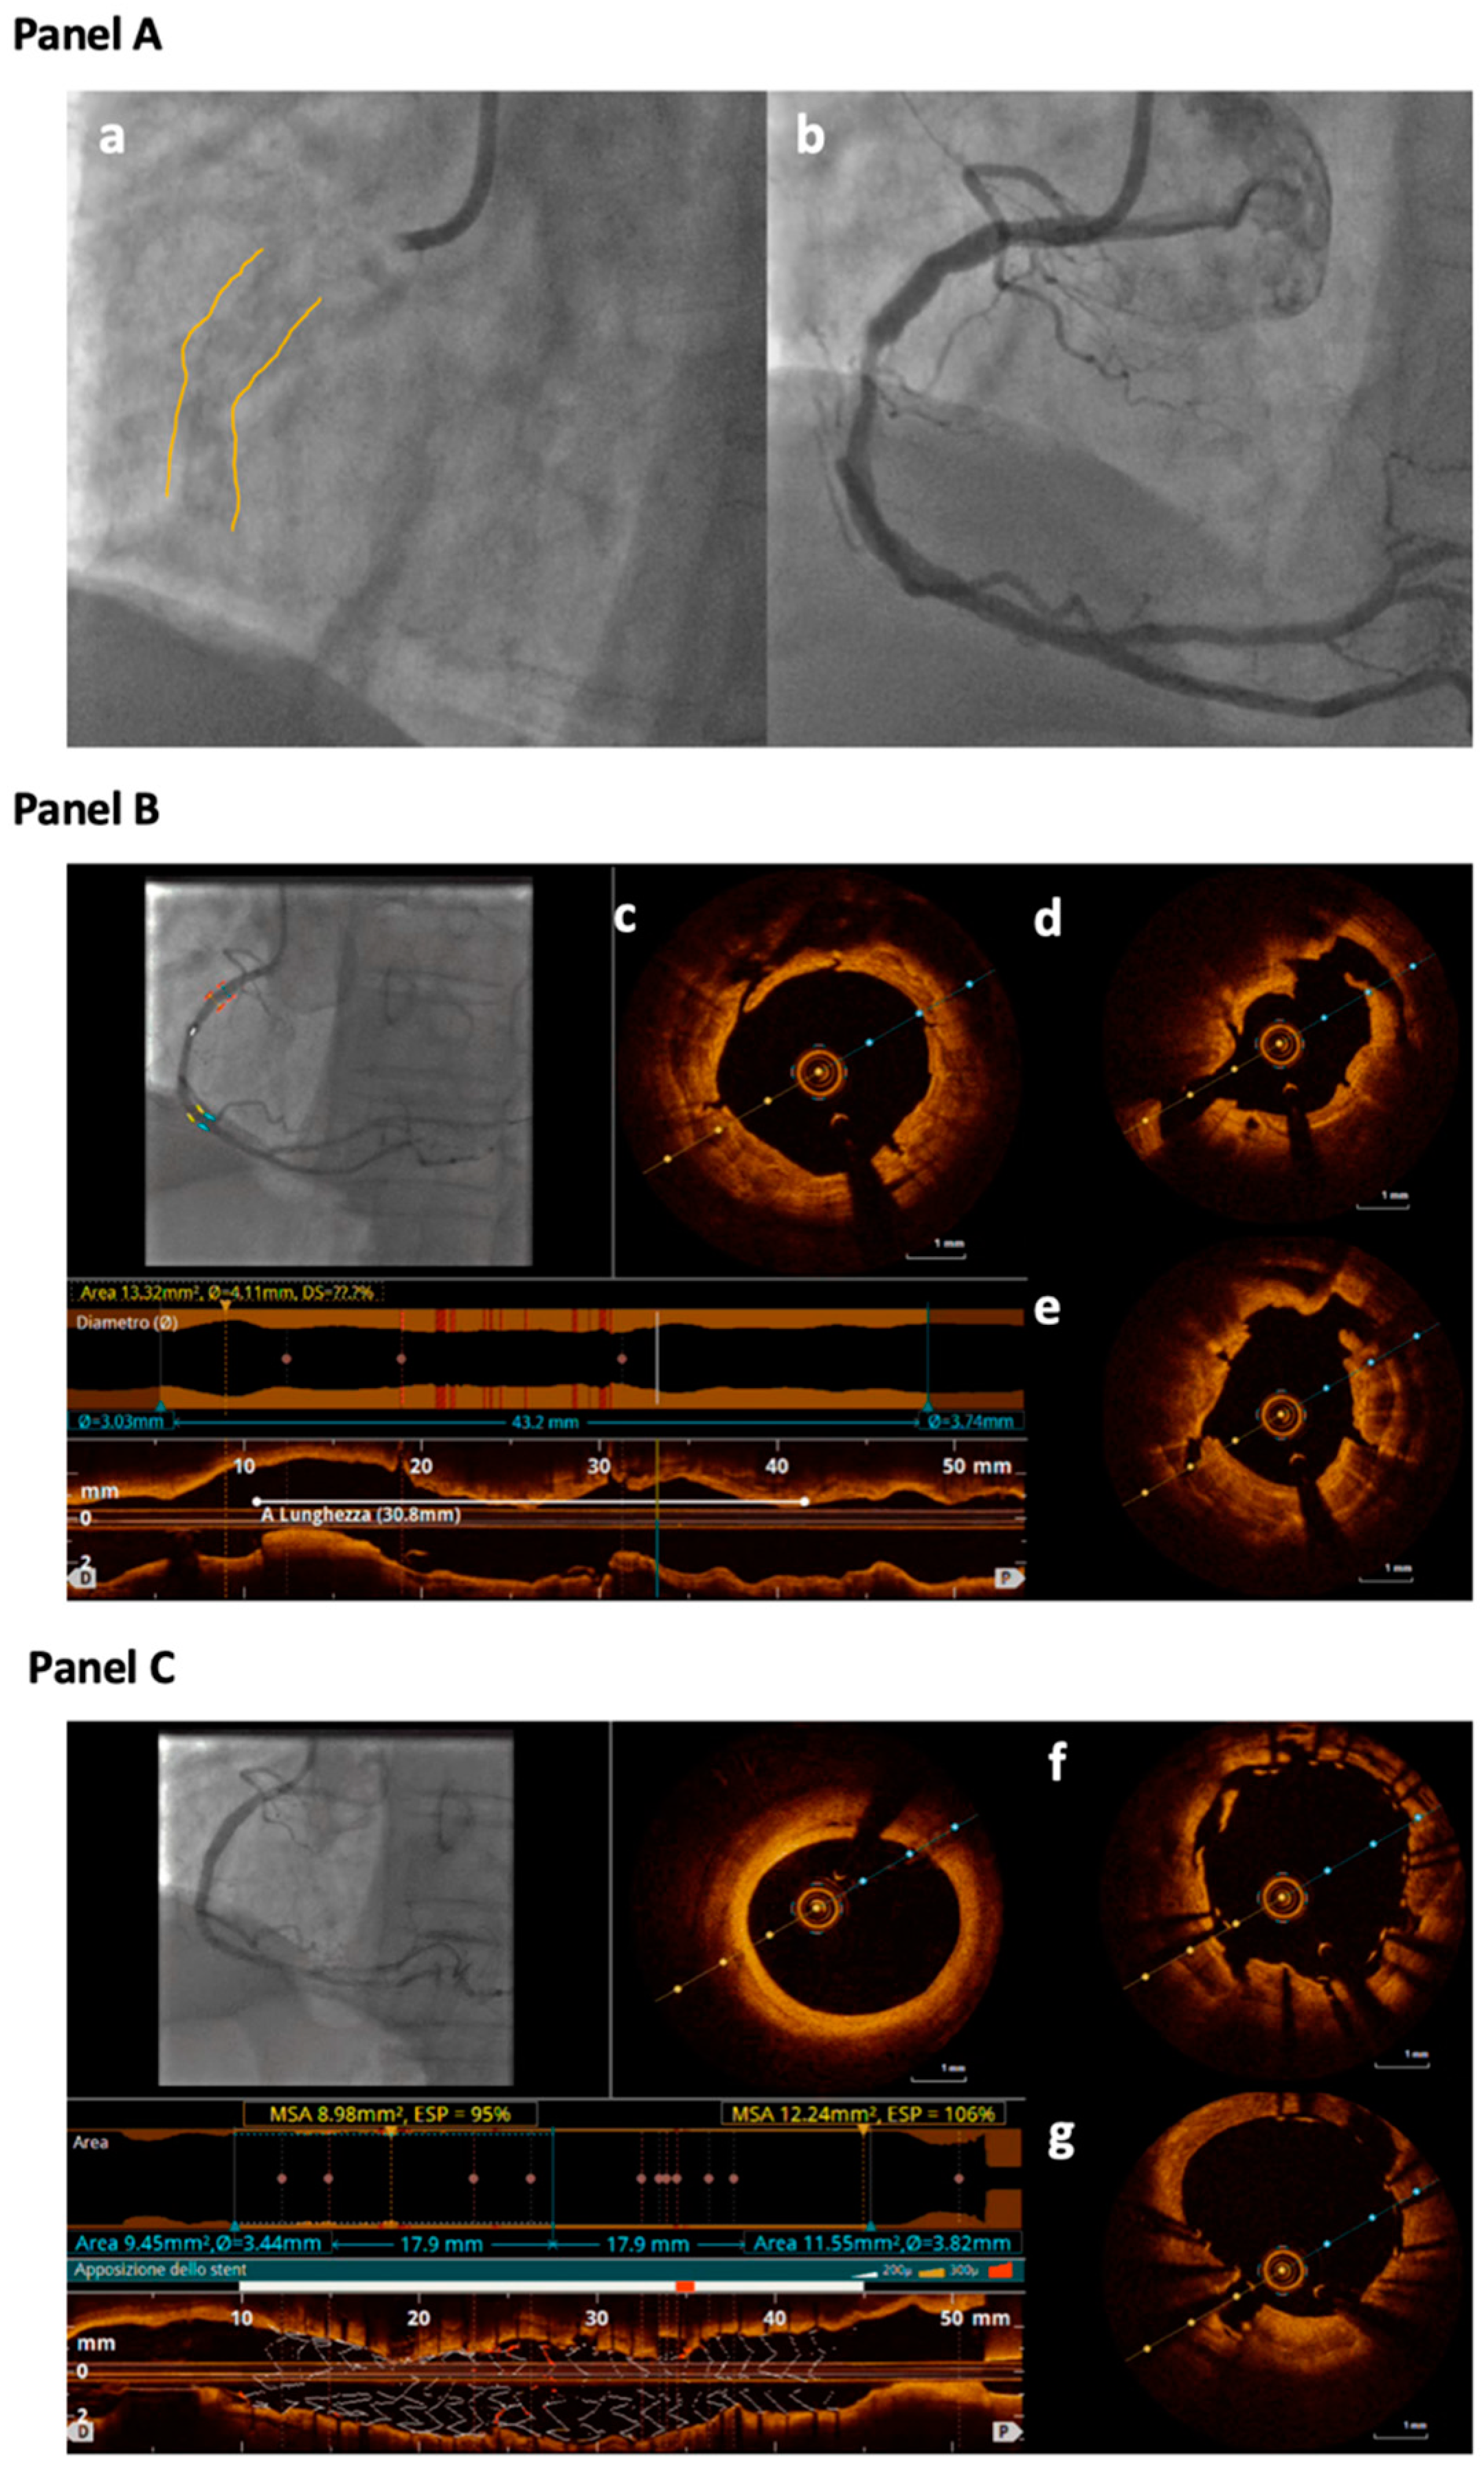

3.4. Optical Coherence Tomography (OCT)

4. Imaging-Guided Plaque Modification

- Fujino, A.; Mintz, G.S.; Matsumura, M.; Lee, T.; Kim, S.Y.; Hoshino, M.; Usui, E.; Yonetsu, T.; Haag, E.S.; Shlofmitz, R.A.; et al. A new optical coherence tomography-based calcium scoring system to predict stent underexpansion. EuroIntervention 2018, 13, e2182–e2189. [Google Scholar] [CrossRef]

- Räber, L.; Mintz, G.S.; Koskinas, K.C.; Johnson, T.W.; Holm, N.R.; Onuma, Y.; Radu, M.D.; Joner, M.; Yu, B.; Jia, H.; et al. Clinical use of intracoronary imaging. Part 1: Guidance and optimization of coronary interventions. An expert consensus document of the European Association of Percutaneous Cardiovascular Interventions. Eur. Heart J. 2018, 39, 3281–3300. [Google Scholar] [CrossRef]